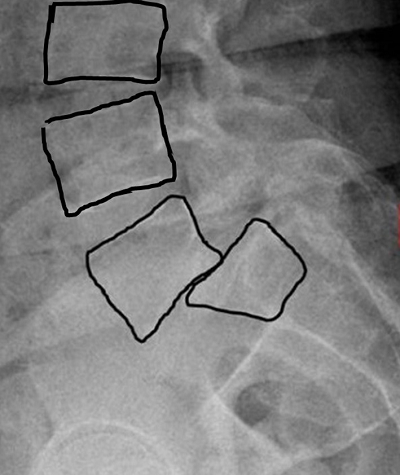

▲척추전방전위증은 위쪽 척추 뼈가 아래쪽 척추 뼈의 앞쪽으로 미끄러져 뼈의 정렬이 어긋나고 통증을 유발하는 질환이다.

우리 몸의 척추는 마치 벽돌을 쌓듯이 위, 아래 척추 뼈의 정렬이 맞아 떨어져야 한다. 하지만 척추가 약해지면 위쪽 척추 뼈가 아래 척추 뼈의 앞쪽으로 미끄러지며 움직이게 된다. '척추 뼈가 몸의 앞쪽(전방)으로 미끄러져 움직인다(전위)'하여 이러한 질환을 척추전방전위증이라고 부른다.